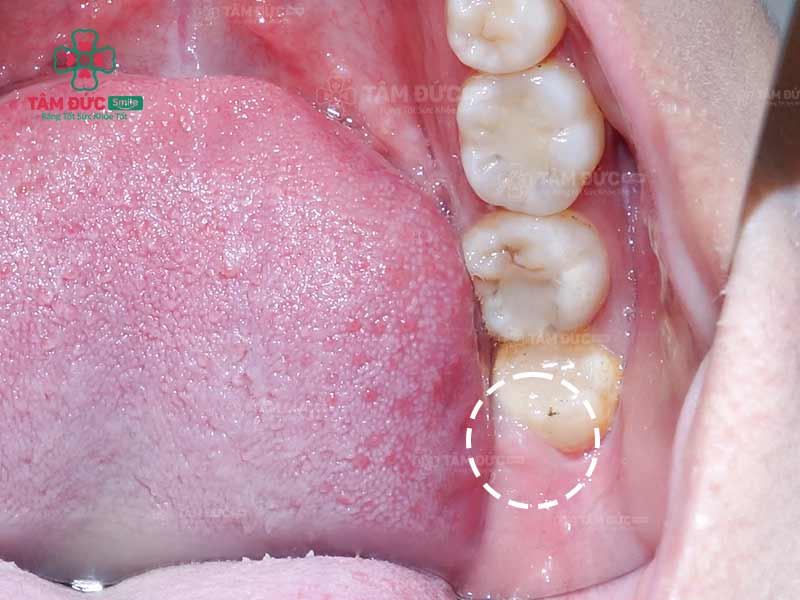

Răng khôn mọc đâm vào răng số 7

Răng khôn mọc ngầm làm sưng nướu